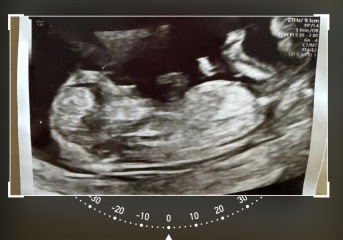

12-week scan, any guesses whether baby is a boy or girl?

12 weeks scan boy or girl any guesses x

I reckon boy x